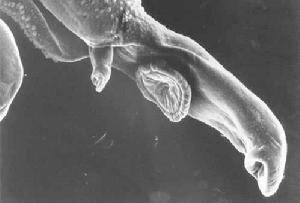

血吸蟲---這是寄生蟲血吸蟲的掃描電子顯微照片。成年 血吸蟲(Schistoso-ma)。也稱“裂體吸蟲”。吸蟲綱,裂體吸蟲科。雌雄異體。雄蟲乳白色,長7~21毫米,體兩側向腹面捲曲,形成小槽,稱“抱雌溝”,用以夾抱雌蟲。雌蟲後半部褐色,纖細如絲,長12~23毫米。寄生在人和多種哺乳動物門靜脈系統的小血管內,引起血吸蟲病。雌蟲在腸壁附近產卵,卵呈橢圓形,可穿透腸壁,隨糞排出。在水中孵出毛蚴,進入中間宿主釘螺體內,發育增殖成許多胞蚴,由胞蚴產生許多尾蚴後,逸出螺體,遇入水的人、畜即由皮膚侵入體內。